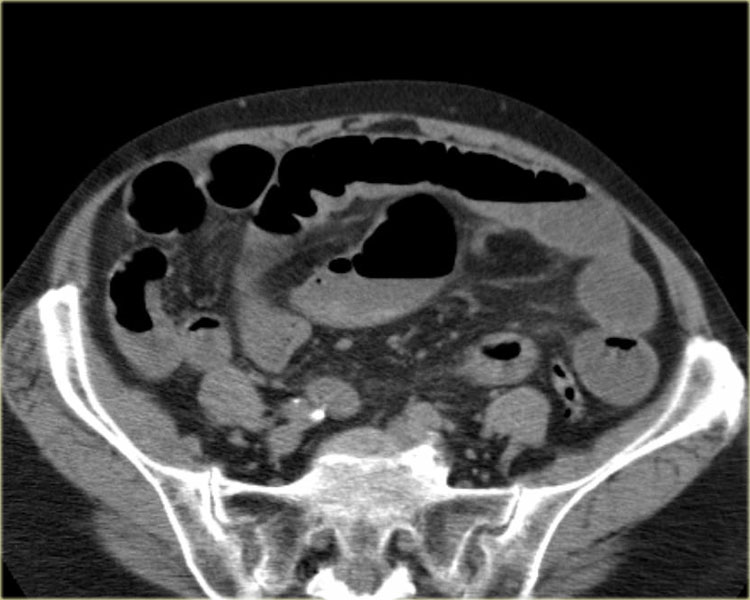

Bên trái là các hình ảnh CT bổ sung của cùng bệnh nhân nêu trên.

Hãy quan sát các hình ảnh này, tìm kiếm các dấu hiệu chính rồi tiếp tục.

Đầu tiên, chúng ta thấy đại tràng xuống xẹp và đại tràng lên không giãn, do đó đây không thể là xoắn đại tràng sigma.

Thứ hai, chúng ta thấy một cấu trúc hình mỏ chim ở góc phần tư dưới bên phải, đây là vị trí xoắn của ruột.

Ở góc phần tư dưới bên trái, chúng ta thấy manh tràng giãn.

Tái tạo ảnh mặt phẳng coronal có thể rất hữu ích trong việc thể hiện toàn cảnh tổn thương.

Xoắn manh tràng xảy ra do manh tràng xoắn quanh đại tràng lên, dẫn đến tắc ruột non.

Mạc treo ruột có nền hẹp và dài là yếu tố thuận lợi gây xoắn.

Xoay ruột giữa không hoàn toàn là một yếu tố nguy cơ.

Nhồi máu thường là hậu quả của ứ trệ tĩnh mạch, trong khi nguồn cung cấp động mạch hiếm khi bị ảnh hưởng.

Xoắn manh tràng chiếm khoảng 25% các trường hợp xoắn đại tràng.